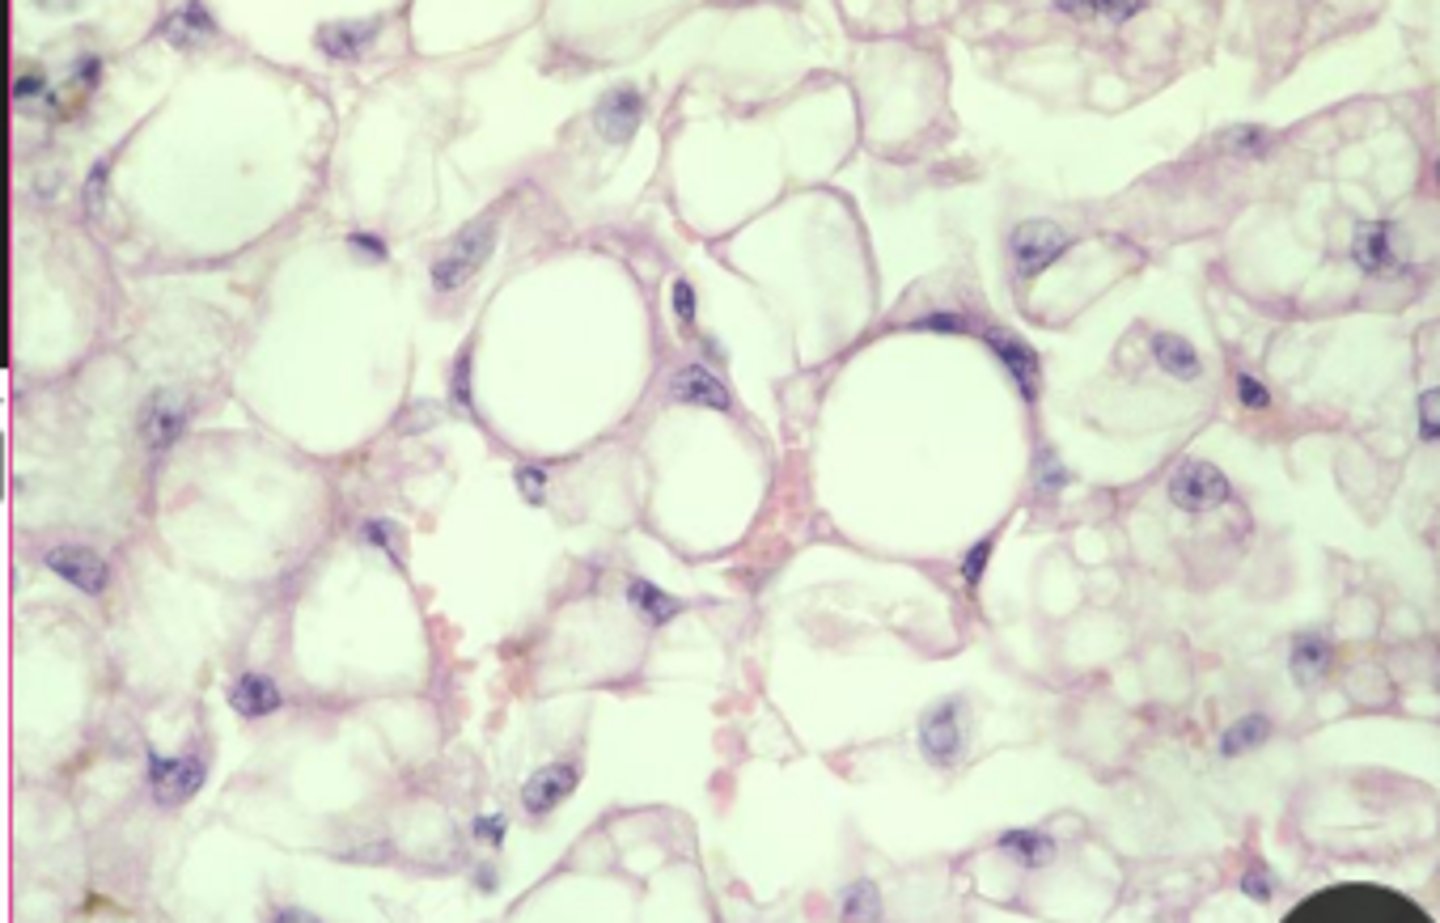

globoid cell leukodystrophy

knowt flashcard image

sphingolipidoses

enzymes associated with different products

what characterizes a storage disease as lysosomal?

deficiency of lysosomal acid hydrolases

what could cause lysosomal storage diseases?

incomplete breakdown of substrates

accumulation of partially degraded, insoluble metabolite within lysosomes